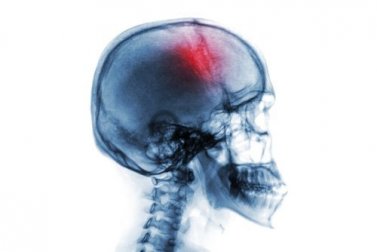

Acidente vascular cerebral (AVC): causas e tratamento

Um acidente vascular cerebral (AVC) é uma parada cerebrovascular que é desencadeada, principalmente, por um processo de isquemia cerebral. Durante esse processo, parte da massa cerebral morre devido a uma falha no suprimento sanguíneo.

A isquemia ocorre, portanto, quando o cérebro não recebe oxigênio suficiente. Essa situação pode ocorrer, por exemplo, pela presença de coágulos sanguíneos que bloqueiam a irrigação cerebral.